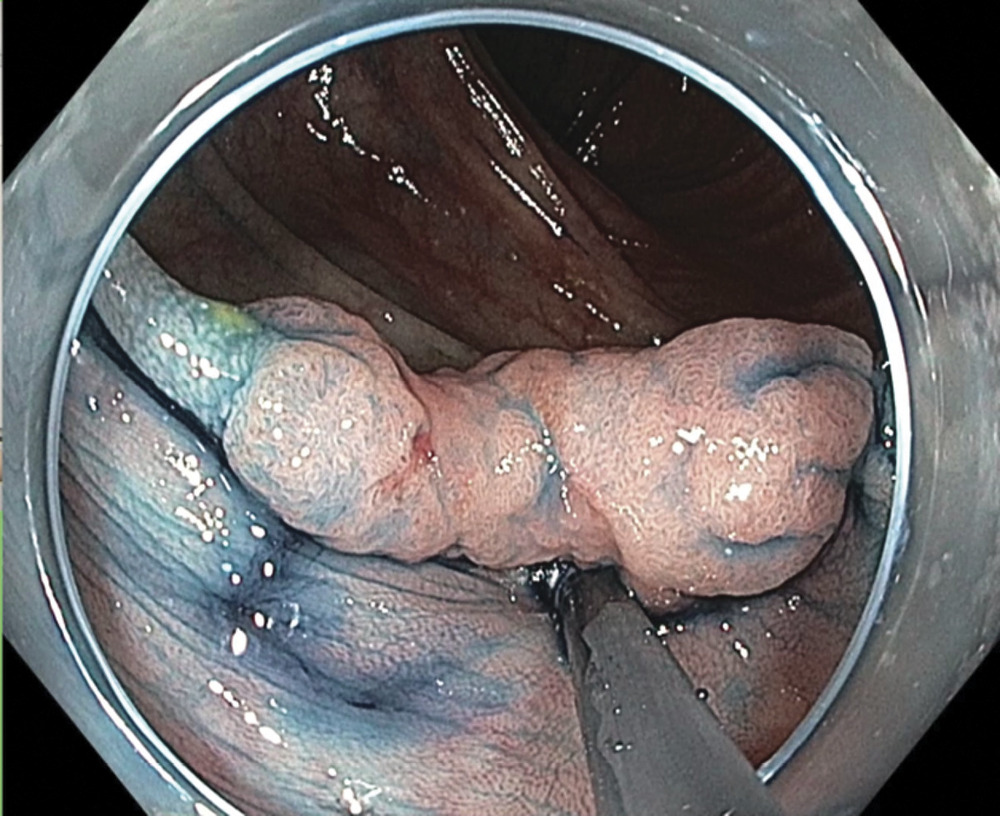

Пациент С., 65 лет. Диагноз: мультицентрический синхронный рак толстой кишки. Рак поперечной ободочной кишки 0-IIa+IIc. Состояние после эндоскопического удаления раннего рака восходящей ободочной кишки 05.2017 (высокодифференцированная аденокарцинома в аденоме, pG1, m3, L0, V0, R0). При обследовании у пациента выявлена латерально распространяющаяся опухоль поперечной ободочной кишки размером 2,0×1,5 см, негранулярный тип. Гистология: умеренно дифференцированная аденокарцинома в аденоме (рис. 6).

При проведении анализа проф. Ю. Сайто установил, что структура поверхности опухоли имеет тип IV по классификации S. Kudo, что соответствует инвазии только в поверхностный подслизистый слой sm1 (рис. 7).

Следующий этап — лечебный. Была выполнена эндоскопическая резекция слизистой оболочки с опухолью с диссекцией в подслизистом слое ESD (рис. 8, 9,